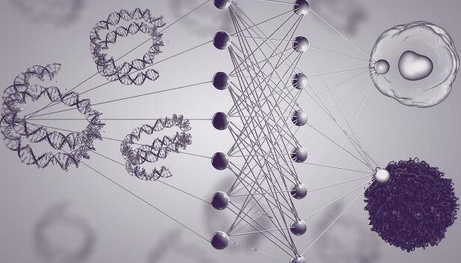

双靶点成功治疗多发性骨髓瘤

记者6月21日获悉���,南京传奇生物科技有限公司与西安交通大学第二附属医院合作展开的多靶点CAR-T疗法临床试验表现出惊人的客观缓解率,在近日举行的美国临床癌症学会年会上��,该疗法引起与会专家的高度评价和瞩目�。“患病后��,人体免疫细胞无法识别肿瘤细胞��,导致肿瘤快速复制转移病情扩散”���,南京传奇生物科技有限公司首席科学家兼创始人范晓虎说����,这种CAR-T疗法的特点是双靶点治疗,“目前大多数CAR-T疗法是一个靶点����,就像用一只手去抓球极易脱手,而双靶点相当于两只手去抓球����,成功率大大增加”。多发性骨髓瘤是三大血液系统恶性肿